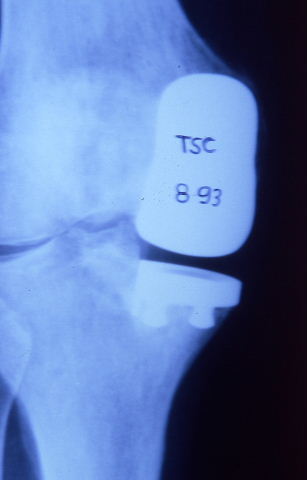

Prótesis completa de rodilla. Situación postquirúrgica.

Prótesis completa de rodilla. Situación postquirúrgica. Lateral.

Prótesis completa de rodilla.Lateral.

Prótesis completa de rodilla. Frontal.